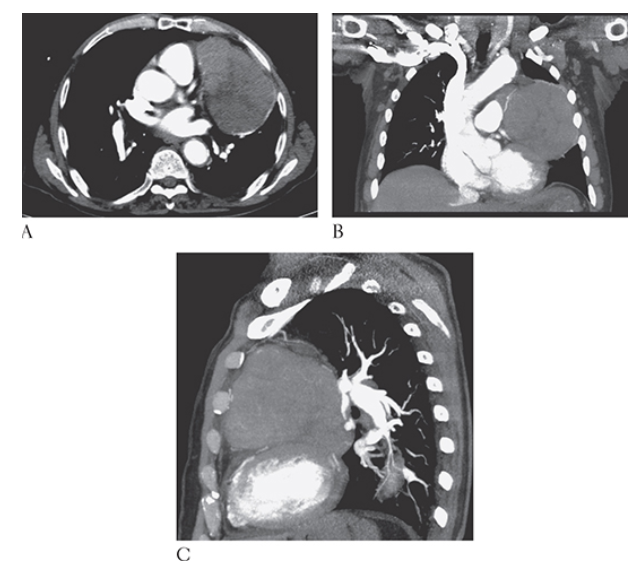

What is A

Thymoma. Posteroanterior (PA) and lateral

What is B

Thymoma. Posteroanterior (PA) chest radiographs show a large left anterior mediastinal mass projecting over the left lung.

Aortic Coarctation. CTA sagittal oblique MPR of the chest shows severe narrowing in a different patient.

Aortic Coarctation. CTA axial of the chest at the level of the severe narrowing in the same patient as Figure 1 shows multiple collaterals and enlarged intercostal arteries with rib notching.